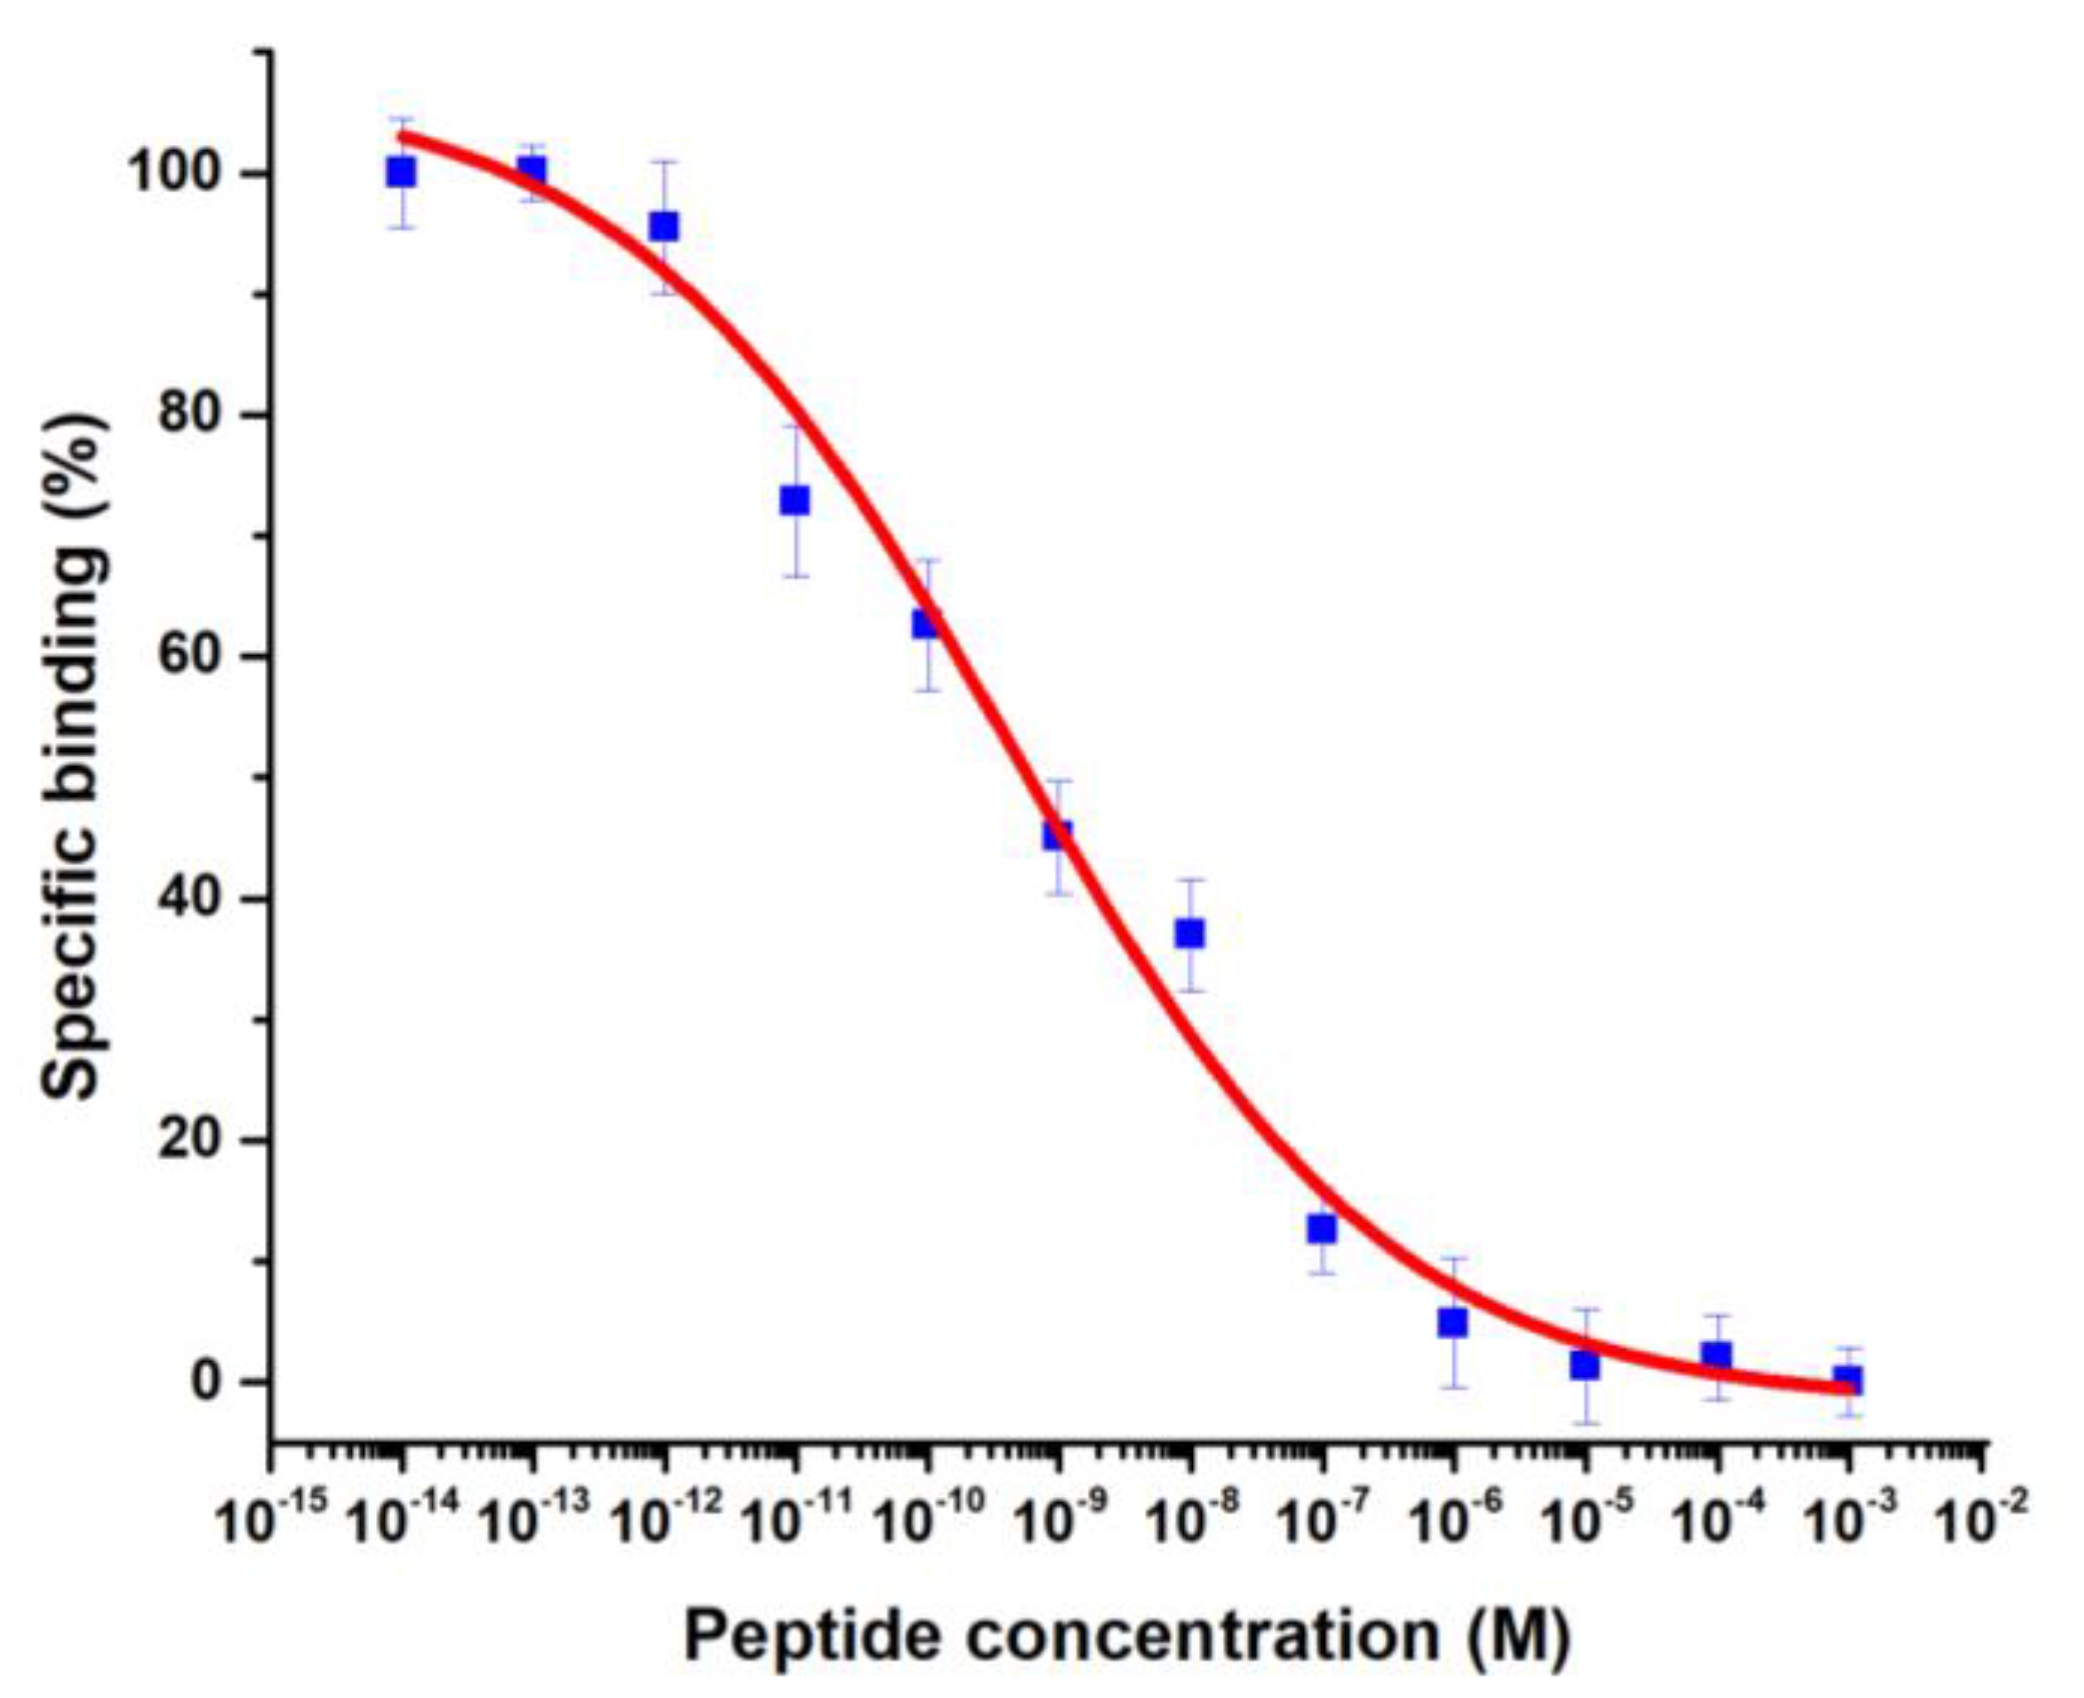

3.4.1. Binding Assay